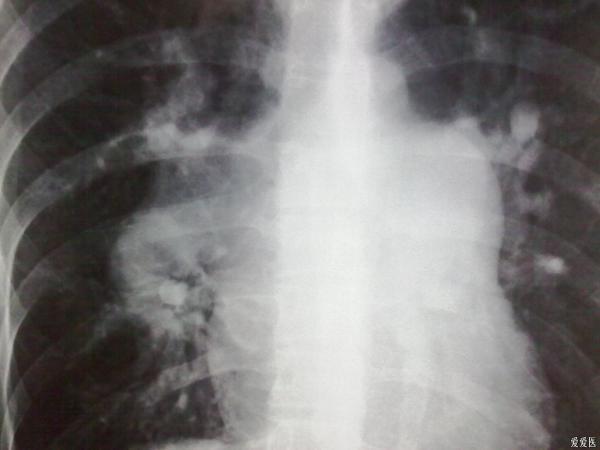

典型肺动脉高压胸片(室间隔缺损)

1、肺动脉段突出。2、肺血管纹理变少了。3、右心室大,心尖圆钝。。